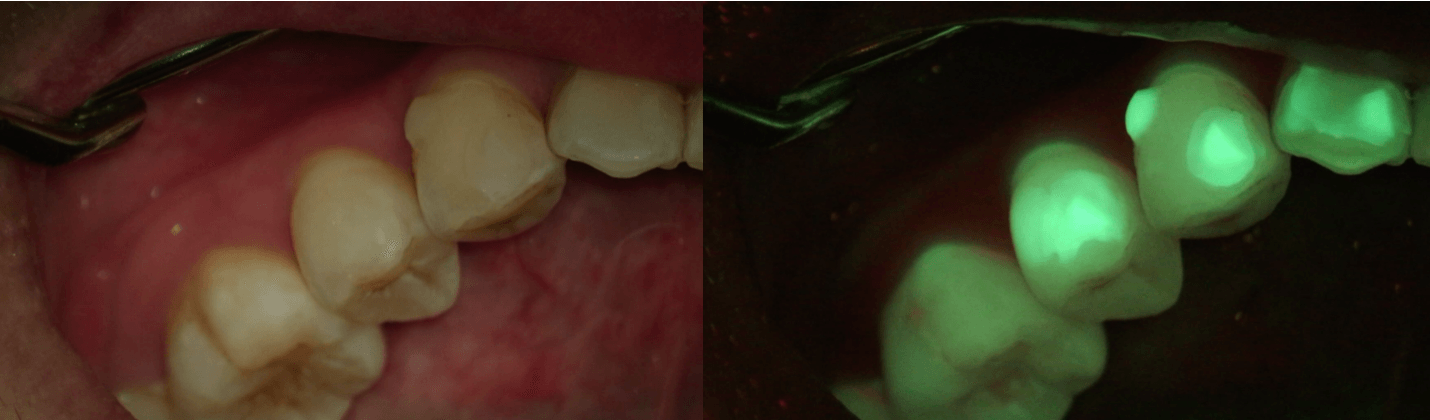

Problemer som vanligvis er usynlige til de blir akutte:

Skjult tannråte

Riss og sprekker i tannemaljen

Opptil 20× forstørrelse. Avdekker det som er usynlig for det blotte øye.

"Det øyet ikke ser —

kan mikroskopet avsløre"